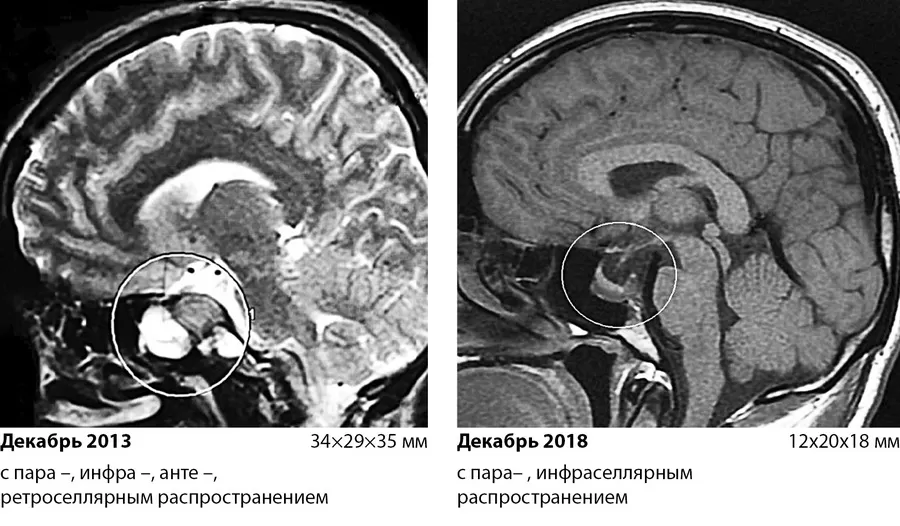

В дальнейшем на фоне постоянного приема вышеуказанной дозировки каберголина сохранялась положительная динамика: поддержание уровня ПРЛ в пределах целевых значений (ПРЛ от 18.01.2017 301.3 мЕд/л (референсный диапазон 60– 510)), уменьшение размеров аденомы (рис.1), что позволило в январе 2017 рекомендовать начать постепенное снижение дозы препарата.К декабрю 2018 г пациент принимал каберголин в дозе 0.5 мг в неделю, уровень ПРЛ находился в пределах нормы – 256 мМЕ/л, по данным МРТ отмечалось дальнейшее уменьшение размеров пролактиномы: инфра –, параселлярное распространение, размеры 12х20х18 мм, снижение ретроселлярного распространения (рис.2). При эхокардиографическом исследовании структурных и функциональных нарушений не выявлено. В настоящее время наблюдение за пациентом продолжается.

Рис. 2. Изменение размеров и распространения образования гипофиза через 5 лет терапии каберголином